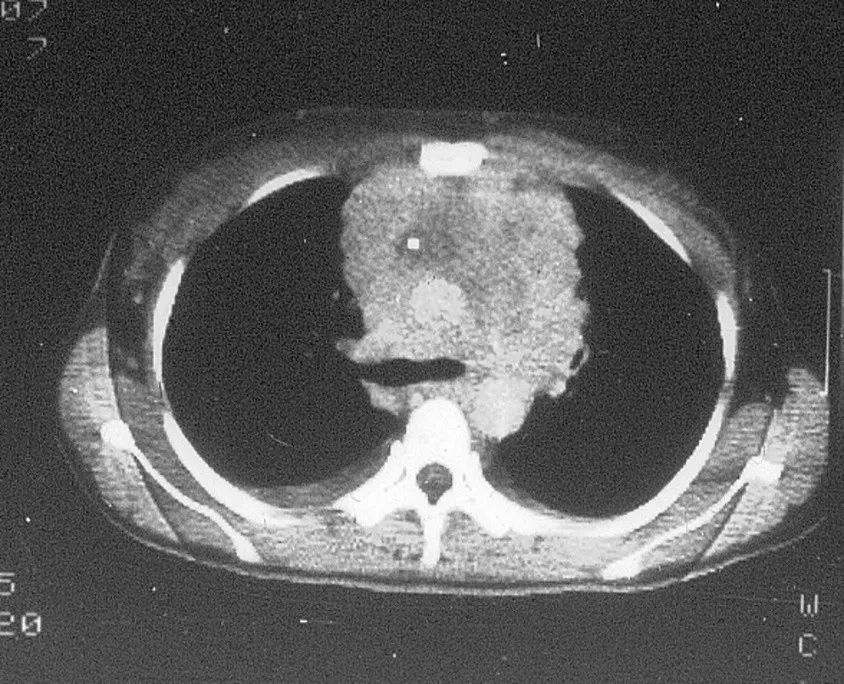

3.畸胎瘤

部位:前纵隔实性肿物;

密度:不均,可有脂肪、钙化、牙齿及骨骼影;皮样囊肿为液性密度,可见蛋壳样钙化;

形状:圆形或类圆形,边缘光滑;良性多;恶性者呈边缘不清,可坏死,周围脂肪间隙消失;

CT、MRI多数可明确诊断。

畸胎瘤影像学表现